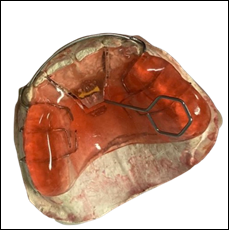

Se tuvo una conversación sobre el comportamiento de la paciente con su acudiente en caso de que se tuviera que colocar aparatología ortodóntica removible. Se llega a la conclusión de colocar dos aparatos: Hawley superior modificado con tornillo de expansión, planos de altura y flechas y Hawley inferior modificado con flechas y helicoides. (2,3)

Figura 13. Hawley superior modificado con tornillo de expansión